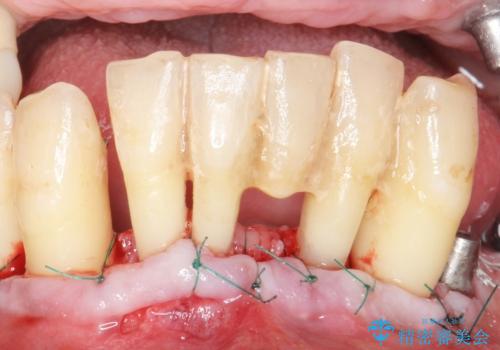

精査したところ、全顎的な重度の歯周病により下顎前歯に激しい動揺を認めました。

できるだけ自分の歯を残したいという患者様の強いご希望により、禁煙指導後再生療法(骨を増やす手術))を行いました。

再生療法から1年後リエントリー手術により骨の再生を確認し、骨外科処置(骨を平らにして歯周ポケットの根本的な改善を図る処置)を行ったのち、連結補綴を行いました。

再生療法と骨外科処置により、歯周ポケットは全周2mm以下に改善されました。